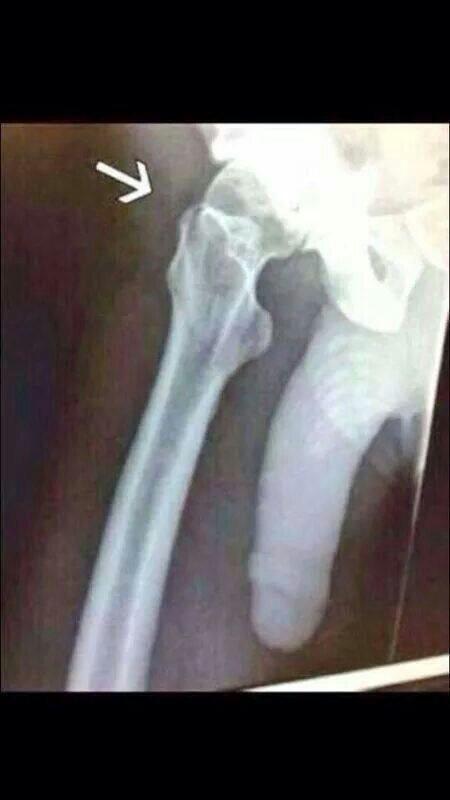

Penile trauma can result from a blunt or penetrating injury, the latter being rarely investigated by imaging methods, almost always requiring immediate surgical exploration. In the erect penis, trauma results from stretching and narrowing of the tunica albuginea, which can undergo segmental rupture of one or both of the corpora cavernosa, constituting a penile fracture.[2]

In the ultrasound examination, a lesion of the tunica albuginea presents as an interruption in (loss of continuity of) the echoic line representing it (Figure 4). Small, moderate, or broad hematomas demonstrate the extent of that discontinuity. Intracavernous hematomas, sometimes without the presence of a tunica albuginea fracture, can be observed when there is a lesion of the smooth muscle of the trabeculae surrounding the sinusoid spaces or the subtunical venular plexus.[2]

Figure 4 A: Ultrasound of the penis, right lateral view. Longitudinal section showing rupture of the tunica albuginea with an adjacent 1.92 cm hematoma (between calipers), due to trauma.[2]

B: Axial T2-weighted turbo spin-echo magnetic resonance imaging scan showing left-sided discontinuity of the tunica albuginea (arrow), secondary to fracture.[2]